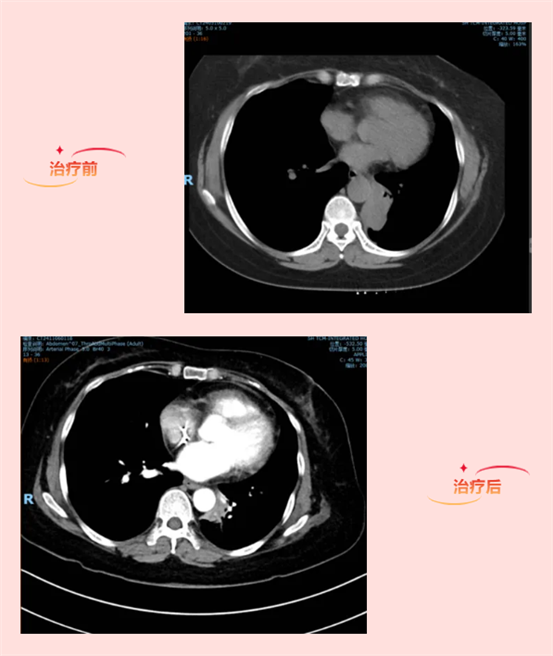

2017年,来自安徽农村的郑女士因触及淋巴结肿块至当地医院就诊,穿刺结果提示肺癌来源,随经人介绍慕名至我科就诊。直至2019年中旬,郑女士每21天至我科规律化疗,来来往往的的绿皮火车票也攒满了一盒子,但仍无法抵抗病魔的侵袭,病情提示进展。

接诊郑女士时才了解到,原来当年在外院接受临床试验一段时间后,再次肿瘤提示进展,揭盲后发现在化疗联合安慰剂组,于是外院免费提供免疫治疗药物直至此次再次提示肿瘤进展,所幸这段时间也维持了2年多。幸得喜事,家中儿子诞下孙子,但喜不长久,烦恼也接踵而至,媳妇在产后因浆细胞性乳腺炎被迫停止哺乳,郑女士的儿子只得暂且停下手头的工作去照顾媳妇,才1岁多嗷嗷待哺的小孙子也只能喝上了奶粉。可是哪怕是最便宜的奶粉和尿布,这持续大量的开销也让本就家徒四壁的一家更是雪上加霜,全家每天的日常饮食便是白面一碗,再配上点老酸菜。儿子不得不天一亮便外出去十几公里外的镇上务工,常常顾不得吃上早饭,中午也就蹭一顿厂里的盒饭,到了晚上披星戴月到家,囫囵吃上几口稀饭和馍,便累得昏睡过去。而此时摆在郑女士面前的难题,是疾病进展需要再次基因检测,提供具有临床意义的靶点作为靶向药物用药的依据,可完全自费的基因检测费用却成了板上的难题。毕竟有了后代,自己实在不愿再拖累小孙子,7年的生存期已经让她充满感恩。但家人的坚持和鼓励,让她还是决定再来我院,寻求最后一丝帮助。